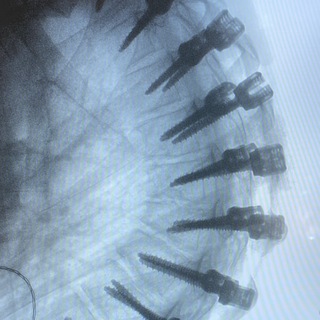

Радиочастотная денервация

Область воздействия: фасеточные суставы позвоночника, крестцово-подвздошное сочленение

Показания: фасеточный болевой синдром, боли в области ПКС

Методика: Заключается в тепловой деструкции нервов, ответственных за болевую импульсацию из дегенеративно-измененного сустава позвоночника.

Этапы: паравертебральное чрескожное введение игл-канюль в область предполагаемой денервации под рентген-контролем. Введение электрода в полость иглы. Тестовое проведение токов, с целью определения безопасности расположении электрода. Финальная термокоагуляция нервов. Введение иглы повторяется для каждого отдельного сустава